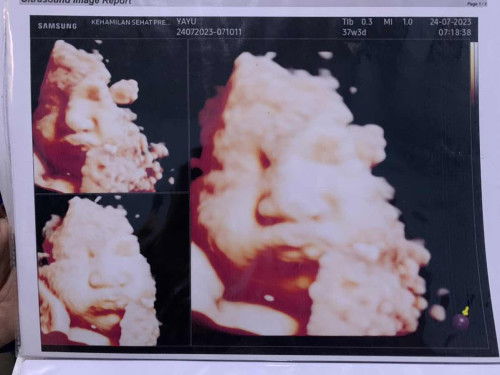

37 weeks 3 days

Semoga segera lahiran ya adek , pas 37w1d pembukaan 1 tp sepertinya sudah hilang pembukaannya krna smpe skrg gak mules .

37w pembukaan 1

Niat cuma kontrol krna jdwalnya balik ke bidan . Udh 37w jadi ada cek lab dan cek panggul . Hasil lab bagus smua, pas cek panggul trnyata pembukaan 1 kepala baby udh kesentuh . Cuma aku blg “biarin lah pembukaan 1 mah bu, wktu abangnya aja ke bidan pas udh pembukaan 6” 😂